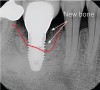

Figure 13  The periapical radiograph taken 7 years post-surgery with indicators of defect fill.

Figure 13

Figure 14  Recurrence of peri-implant bone loss as a result of 2 years of no maintenance, rendering the implant hopeless.

Figure 14